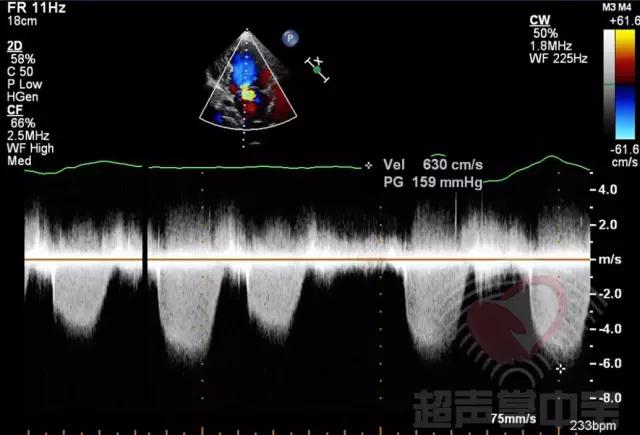

经典病例▏二尖瓣囊肿中竟然全是血液? 图8:CW于囊状物内探及收缩期负向高速湍流,流速6.3m/s,压差159mmHg